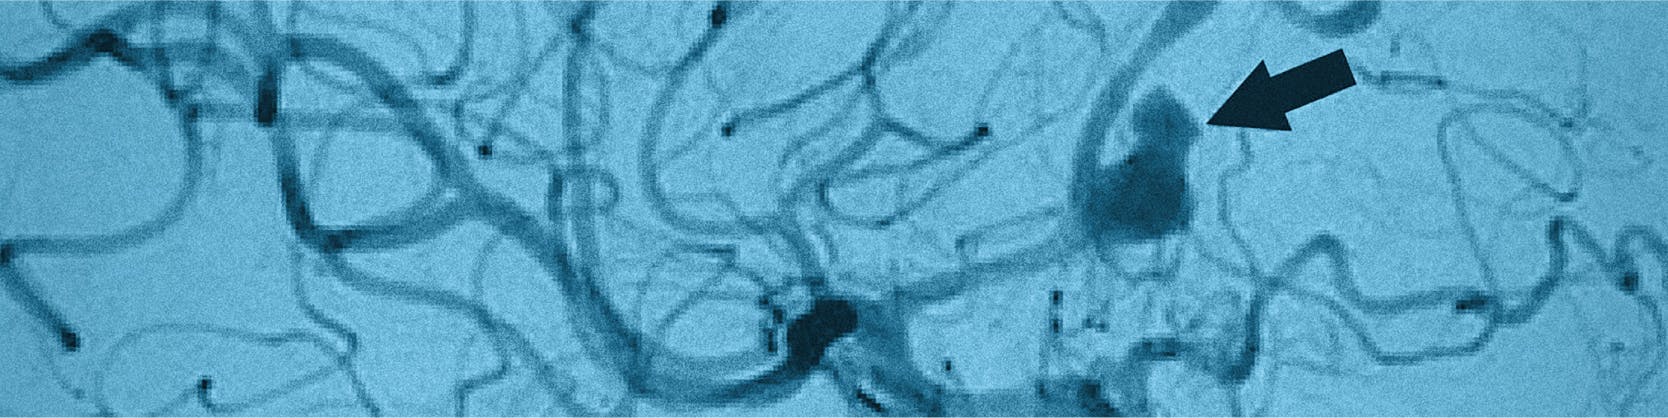

Embolizarea anevrismului cerebral, pe de altă parte, este o tehnică mai puțin invazivă, similară angiografiei, și implică utilizarea unui dispozitiv numit „coil” pentru a închide anevrismul și a bloca fluxul de sânge către acesta, ceea ce îl împiedică să crească în dimensiuni și să se rupă.

Coil-ul este un dispozitiv din platină, extrem de subțire (cel mai mic este mai subțire decât un fir de păr, cel mai gros este de 2 ori mai mare decât grosimea unui fir de păr), foarte flexibil, care umple anevrismul, mulându-se pe el.

- În momentul în care se ajunge la nivelul anevrismului, coil-ul va fi introdus în deschizătura anomaliei vasculare, unde va umple anevrismul, blocând astfel intrarea sângelui total sau parțial. Pot fi necesare mai multe dispozitive pentru obstrucția completă a anevrismului. În timpul intervenției se verifica în permanență localizare cateterului prin angiograme repetate (injectare de substanță de contrast pe cateter care permite vizualizarea cateterelor și a sistemului vascular).

- După ce s-a montat coil-ul, se verifică angiografic rezultatul și, dacă anevrismul a fost închis, se aplică un microcurent care va determina detașarea coil-ului de microcateter.